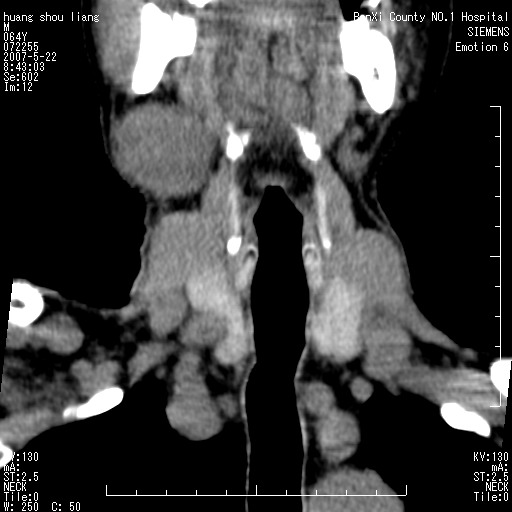

男性,64岁。颈部包块8年。最近增大。

对不起大家,可能是片子发太多有点乱,正常腮腺在下颌角的外侧,颌下腺在下颌体的中部内侧,本例在下颌角内侧偏下,和腺体一点关系都没有,从vrt和mpr上可以很明显看出来,再者肿块是好多粘连在一块的,大家在仔细看看,左侧可能也是吧,我还是考虑为肿大的淋巴结融合在一块,但性质??????

右侧腮腺下部均匀软组织密度肿块,外形不规则,与周围组织分界清晰,考虑右侧腮腺混合瘤或多形性腺瘤。

多考虑颌下腺混合瘤恶变,建议进一步检查,另外楼主重建图像很漂亮。

大家好,病理结果出来了,如大家所说,颌下腺混合瘤。

唉,解剖没学好吧,我诊断错了,不过还是有些不理解回去我在多看看书,谢谢大家的参与,以后我还会奉献好的病例。